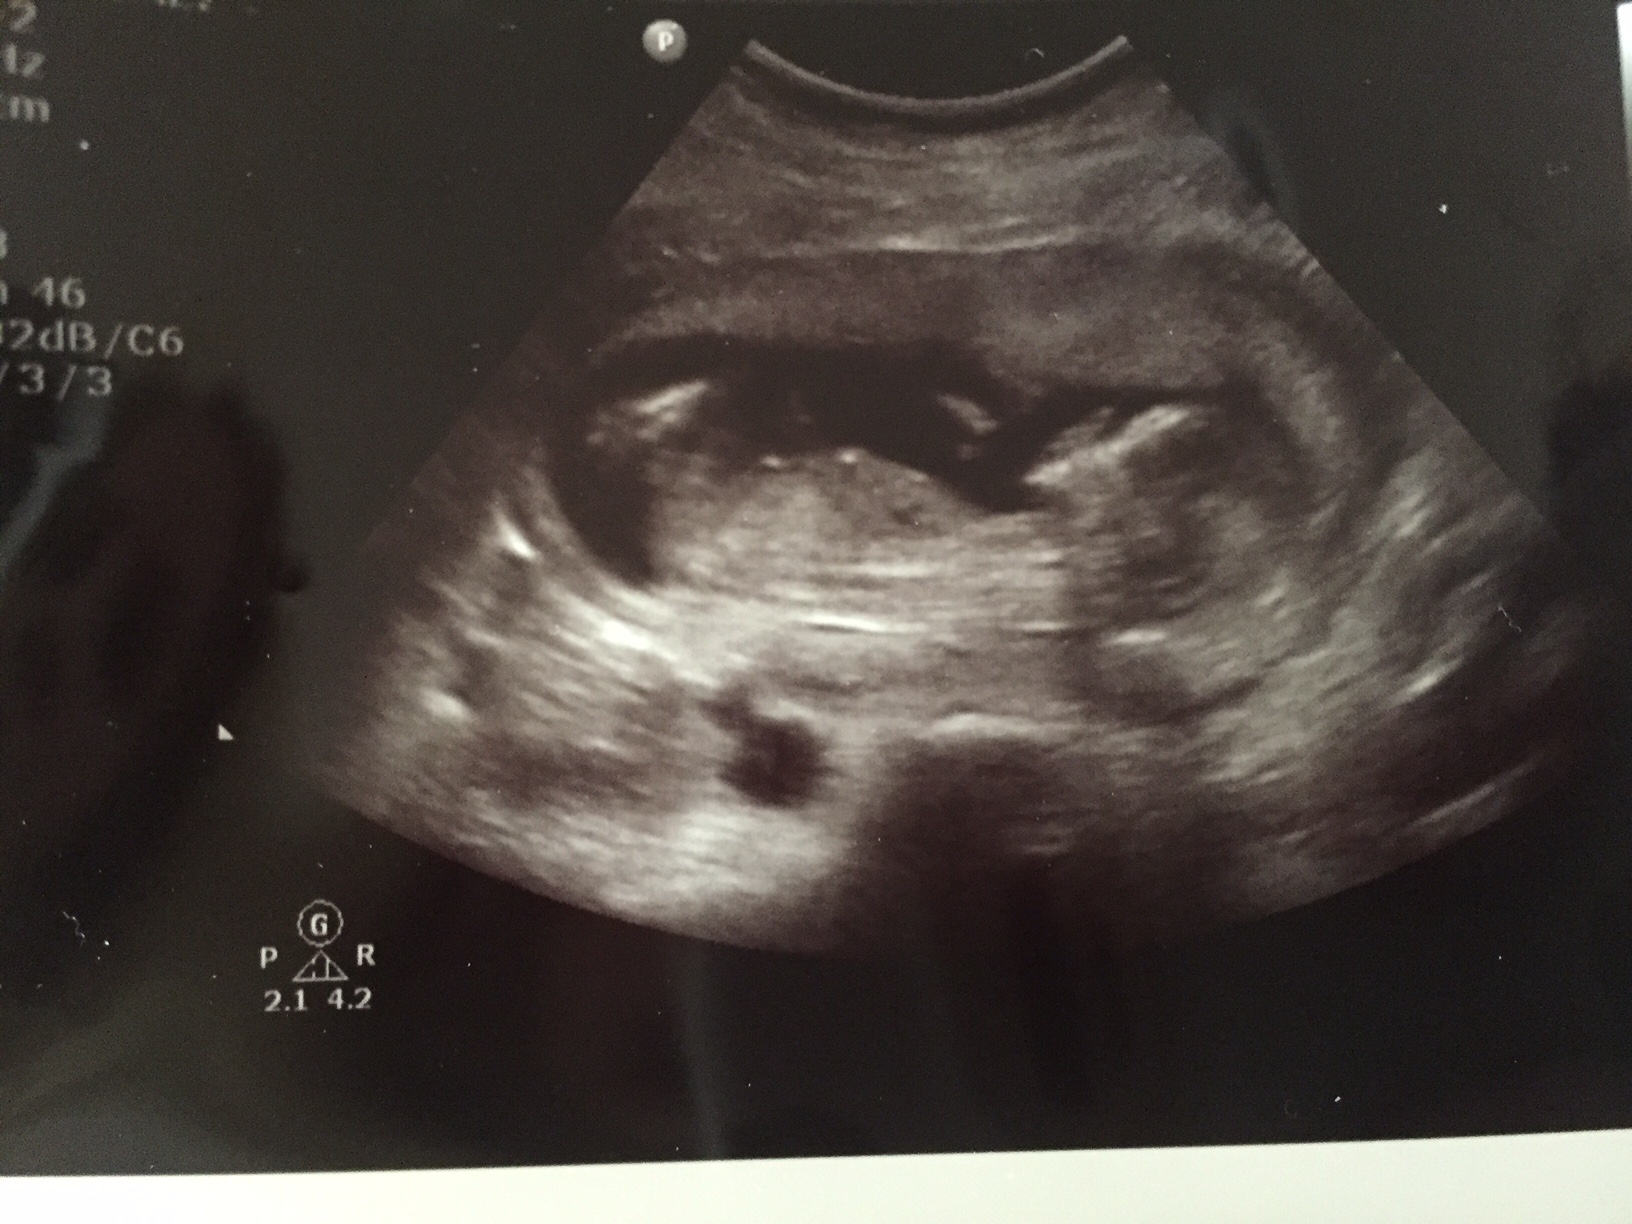

Hi! Just left an ultrasound, I'm 13w4d. The tech is my friend, she thinks boy but wants me to come back next week to confirm. I thought I'd post just to see what you guys think!

This is the shot from underneath that makes her think it's a boy. It's a screenshot from video so not great quality unfortunately.

I also think it's a boy.

Maybe boy? Really not very clear shots ofcthe relevant bits, unfortunately.

I thought the nub looks a bit girly, is that just me??

I think i see stacking of the nub so guess boy